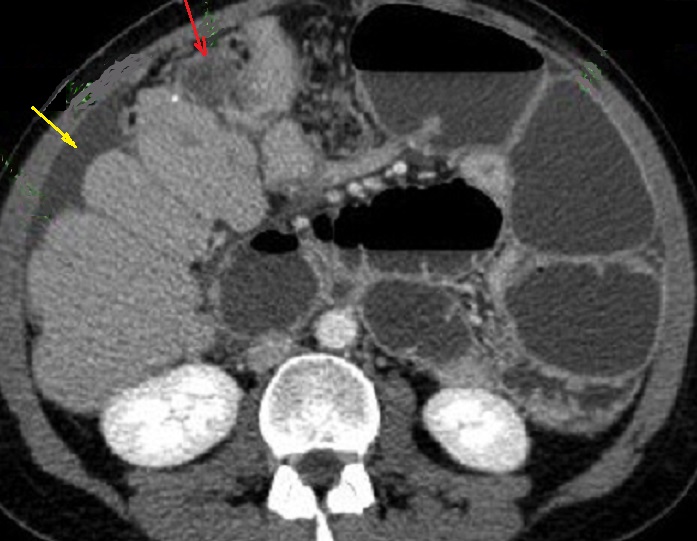

Image

radiologique TDM d'une adenocarcinoma de la tete du

pancreas en coupe axiale . Aspect lesionnel est un

masse hypodense a bord iregulier , l.a tete et le

corp du pancreas est deformation et tumefie .(

fleche rouge ) |

|

Parfois aspect lesionaire

est isodense ( fleche rouge ) . Par sa propiete de

moins de rehaussement de contrast intraveineuse

image radiologique du tumeur serait devenir nettete

sur les coupe TDM plus C+ . Image radiologique TDM

en coupe axiale ( n'a pas de contrast intraveineuse

) |

Aspect radiologique TDM d.'

une adenocarcinoma de la tete du pancreas , c'est un

masse tissulaire hypodensite a bord tres nette situe

a la tete du pancreas ( fleche rouge ) . Par

l'obtacle de la tumefaction le signe indirect

se presenter c'est image de dilatation en amont du

canal pancreatique principale ( fleche jaune ) |

Effet de masse de la tumeur

se donne image de tumefie et deformation de contour

au queue du pancreas ( fleche rouge ) . Image

radiologique TDM d'une adenocarcinoma au queue du

pancreas ( coupe axiale ) |